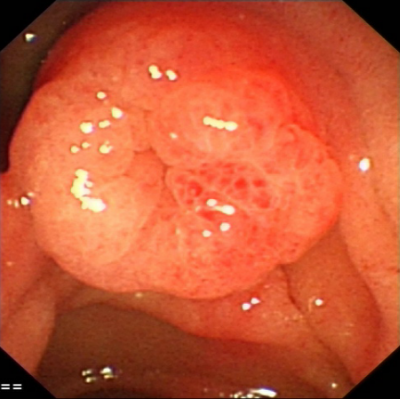

病史摘要:患者为 49 岁女性,因“反复胃肠道息肉切除 17 年余,腹胀 3 天”入院。既往有多部位囊肿,曾行右侧颈部神经鞘瘤手术。家族中父亲、两个哥哥均有结肠息肉相关病史。2008 年首次发现胃底、胃体、结肠等多发性息肉,病理为胃底腺瘤性息肉,此后多次行胃肠镜检查及内镜下息肉切除术。 诊疗过程:入院查体生命体征平稳,慢性病容,上腹轻压痛。2019 年基因检测提示 A